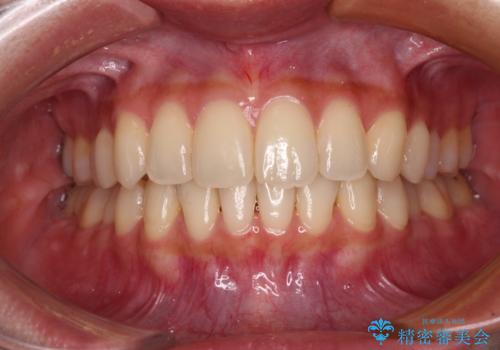

前歯をさげたい 歯を抜かずに マウスピース矯正で治したい

[ インビザライン矯正 ]マイクロインプラント用いた大きな遠心移動

担当医 大元洋佑